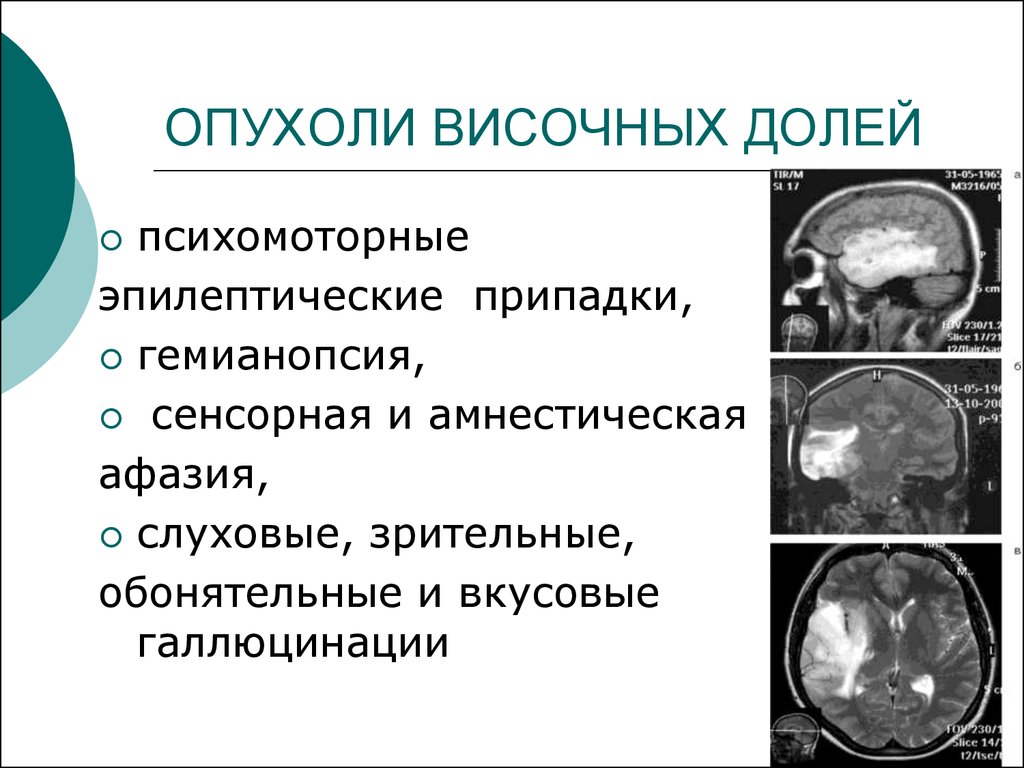

Злокачественные заболевания молочных желез. Новообразование молочной железы. Злокачественная опухоль молочной железы. Доброкачественные новообразования молочной железы. Очаговые симптомы опухоли затылочной доли. Клинические проявления опухоли лобной доли:. Опухоль мозга височной доли симптомы. Опухоль затылочной доли головного мозга.

Очаговые симптомы опухоли затылочной доли. Клинические проявления опухоли лобной доли:. Опухоль мозга височной доли симптомы. Опухоль затылочной доли головного мозга. Гепатомегалия. Симптомы гепатомегалии. Умеренное увеличение печени. Умеренная гепатомегалия.

Злокачественные новообразования печени кт. Объемное образование печени на кт. Клиника опухолей височной доли. Опухоль височной доли головного мозга диагностика. Симптомы поражения лобной доли головного мозга опухоль. Очаговые симптомы опухоли височной доли.

Клиника опухолей височной доли. Опухоль височной доли головного мозга диагностика. Симптомы поражения лобной доли головного мозга опухоль. Очаговые симптомы опухоли височной доли. Проявления поражения теменной доли.. Объемное образование головного мозга.